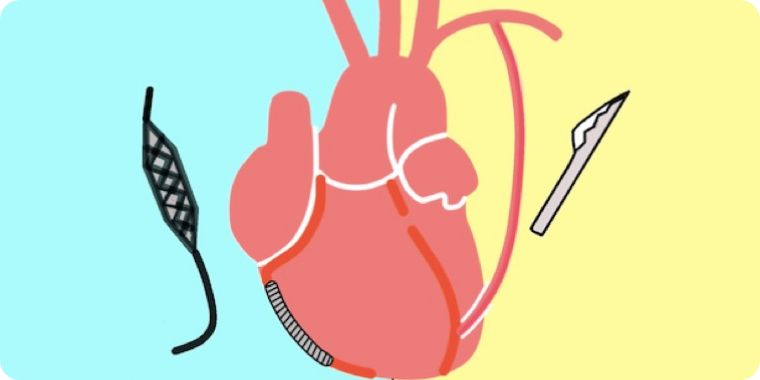

ハイブリッド治療とは本法のMIDCAB (低侵襲直視下冠動脈バイパス術)とカテ―テル治療の長所を組み合わせたものです。

冠動脈バイパス術の長所は、心臓の真ん中を走る一番大事な冠動脈(前下行枝)に内胸動脈をつなげることでカテーテル以上の良好な開存成績が得られる事です。しかし、体の真ん中を大きる切る正中切開法では、体の負担が大きくなってしまいます。一方、ステント治療は静脈を使ったバイパス術とは遜色ない結果であり、体への負担が小さい利点があります。

ハイブリット治療は両者の長所を活かした方法で、高齢者や正中切開が困難な方などには非常に有用な方法と考えております。

循環器内科とのハートチームで患者様の希望に沿った治療を行います。